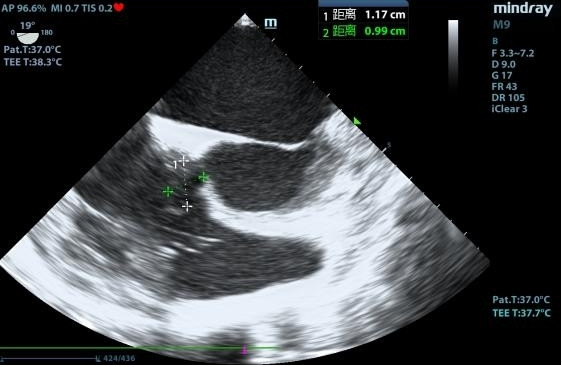

1 资料与方法患者女性,19岁,因“突发胸痛14 h”入院。患者14 h前无明显诱因出现胸骨后疼痛,呈紧缩感,伴有胸闷、呼吸困难,间断咳嗽。近期有听力下降、腹泻病史。8 h前就诊于外院时查体:体温测不出,Bp 53/36 mmHg(1 mmHg=0.133 kPa),呼吸40次/min, 脉搏137次/min,SPO2 93%,神志淡漠,全身皮肤湿冷,黏膜无黄染及出血点,颈静脉无怒张。听诊双肺呼吸音粗,可闻及满肺湿啰音,心音不清,腹部查体无异常,双下肢足背动脉搏动对称。化验结果提示WBC 29.3×109/L,NE 85.4%,TnT 93 ng/L,pro-BNP 2 047 pg/mL,PCT 0.11 ng/mL, 血气分析:pH 7.349,PCO2 31.2mmHg,PO2 67.2 mmHg,HCO3- 17.2 mmol/L,Lac 5.7 mmol/L。心电图提示:窦性心动过速、AVR导联ST段抬高,余导联ST段压低;床旁心脏超声提示EF 52%,二尖瓣中度返流、三尖瓣中重度返流,未见室壁节段性运动性异常。考虑心源性休克,原因尚不明确,给予机械通气、血管活性药物、补液等抗休克治疗,同时联系本院急诊ECMO团队,本院急诊ECMO团队到达现场后,患者突然出现室颤,给予胸外按压及电除颤后逐渐恢复窦律,立即进行V-A ECMO上机指征及预后评分SAVE评分评估,符合V-A ECMO上机适应证,约30 min成功上机运转,流量3.5 L/min,复查外周动脉血气分析: pH 7.305,PCO2 21 mmHg,PO2 73.4 mmHg,HCO3- 10.5 mmol/L,Lac 8.4 mmol/L。后转运至本院急诊病房,转运途中行生命体征、血气分析、ACT等常规监测,至病房后患者ECMO支持下血压仍需大剂量血管活性药物维持且脉压差较小,观察ECMO动静脉管路颜色极为接近,床旁经胸心脏超声提示主动脉瓣重度返流,为明确原因立即行急诊CT检查及床旁经食道超声心动图检查。本院肺CT(图 1)提示肺水肿,床旁经胸心脏超声提示主动脉瓣大量返流但心室收缩可,请超声影像科进一步行床旁经食道超声检查提示无冠窦呈瘤样凸向右房侧,瘤壁上可见宽约0.6 cm破口;主动脉瓣舒张期无冠瓣脱向左室流出道侧(图 2、图 3)。立即请心血管外科会诊,急诊行主动脉瓣机械瓣膜置换术+主动脉窦修补术+房间隔造口术+主动脉球囊反搏置入术+心脏起搏器置入术,术中探查与经食道超声所见相符(图 4、图 5),考虑左心功能差,左心压力较高,行房间隔造口术。术后复查胸片肺水肿基本消失(图 6),继续呼吸机与ECMO支持,因患者肺功能良好,自主呼吸良好,为减少呼吸机相关肺损伤、呼吸机相关肺炎等发生,术后第4天神志清醒后拔除气管插管,机械通气减轻左心前后负荷的作用去除后,继续ECMO与IABP支持,ECMO增加左心后负荷时IABP可降低左室后负荷,达到左心减压的目的,术后第10天心功能恢复,下调ECMO流量后循环可维持,予以撤离ECMO,术后第12天撤离IABP,后停用肝素持续泵入抗凝,达肝素皮下注射联用华法林口服抗凝3 d后,单用华法林口服抗凝,维持INR达标,在康复期间患者活动时左下肢疼痛,左侧足背动脉搏动减弱,下肢动静脉超声提示左侧股浅动脉血栓形成,期间增加华法林剂量后血栓未见明显变化,后行下肢股浅动脉切开取栓术,术后33 d患者完全康复顺利出院。

| 图 3 经食道超声心动图 |

主动脉根部造影为诊断主动脉窦瘤的“金标准”[10], 但本例患者生命体征不稳定,外出检查需携带呼吸机及ECMO机器,转运风险较大,因此采用床旁心脏超声检查是非有创检查的最佳手段之一。本案例外院经胸心脏超声提示三尖瓣中重度返流,入院后床旁经胸心脏超声仅发现主动脉瓣重度返流,仍无法明确心源性休克原因,联系超声影像科通过经食道超声心动图发现无冠窦瘤破裂入右心房才最终明确诊断。主动脉窦瘤的诊断需要技术高超且临床经验丰富的超声科医生,也反映出急诊科医生需学习掌握经食道超声心动图技术。